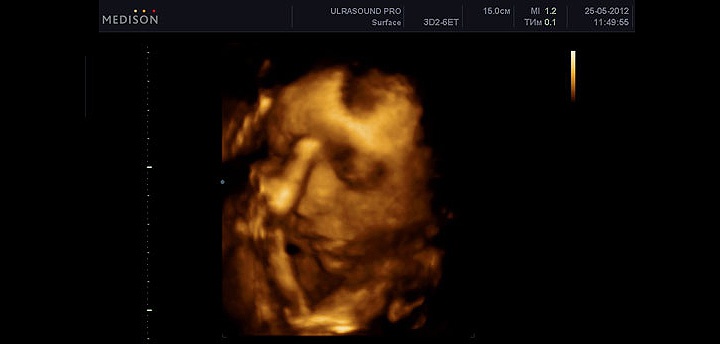

УЗИ на 39 неделе беременности

На 39 неделе УЗИ не требуется, кроме отдельных случаев для оценки состояния плода и плаценты.

При УЗИ оценивается структура плаценты, которая на этом сроке становится второй или третьей степени зрелости, но продолжает активно транспортировать антитела к малышу.

Фетометрия (размеры плода) при УЗИ на 39 неделе беременности в норме

- БПР (бипариетальный размер) 88–102 мм.

- ЛЗ (лобно-затылочный размер) 109–129 мм.

- ОГ (окружность головки плода) 311–359 мм.

- ОЖ (окружность живота плода) 310–374 мм.

Нормальные размеры длинных костей при УЗИ на 39 неделе беременности

- Бедренная кость 69–79 мм.

- Плечевая кость 61–71 мм.

- Кости предплечья 53–61 мм.

- Кости голени 60–70 мм.